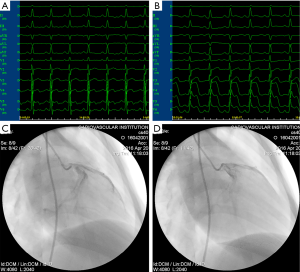

All dogs were anesthetized before being intubated via the intramuscular administration of ketamine (100 mg/kg), followed by an intravenous injection of pentobarbital sodium (30 mg/kg; additional doses of 4 mg/kg were administered when necessary). The dogs were ventilated with ambient air supplemented with oxygen using a respirator (MAO01746; Harvard Apparatus, Holliston, MA, USA), and monitored with 12-lead electrocardiography (ECG). Cardiac catheterization was performed using a Philips FD20 Cath Lab Fluoroscopy Unit (Philips, Andover, MA, USA). A 6.0-Fr sheath was inserted from the right femoral artery. The dogs were systemically anticoagulated with 1,000 IU heparin. A 6.0-Fr angiographic catheter (TERUMO Radifocus OPTITORQUE, Tokyo, Japan) was introduced to select coronary angiograms of the left coronary artery. A 0.014-inch coronary guide wire (TERUMO Runthrough NS, Tokyo, Japan) was inserted beyond the second diagonal branch of the left anterior descending coronary artery. The guide wire was removed when the 1.8-Fr. coronary microguide catheter (TERUMO Finecross MG, Tokyo, Japan) accessed to the site. Left anterior descending coronary artery occlusion was then immediately achieved via an endoluminal injection of 150–350 µm gelatin sponge particles (Alicon Pharm Sci & Tec, Hangzhou, China). Finally, metoprolol (5 mg/kg) and lignocaine (3 mg/kg) boluses were administered. The MI model was considered successful if significant ST-segment elevation was observed on ECG, and if the second coronary angiography confirmed ischemia in the embolism area (Figure 1).